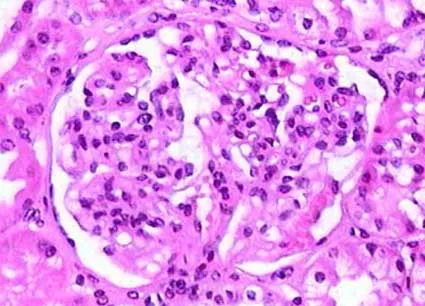

Injúria Renal Aguda (revisão Lancet 2025)

Injúria Renal Aguda (revisão Lancet 2025)